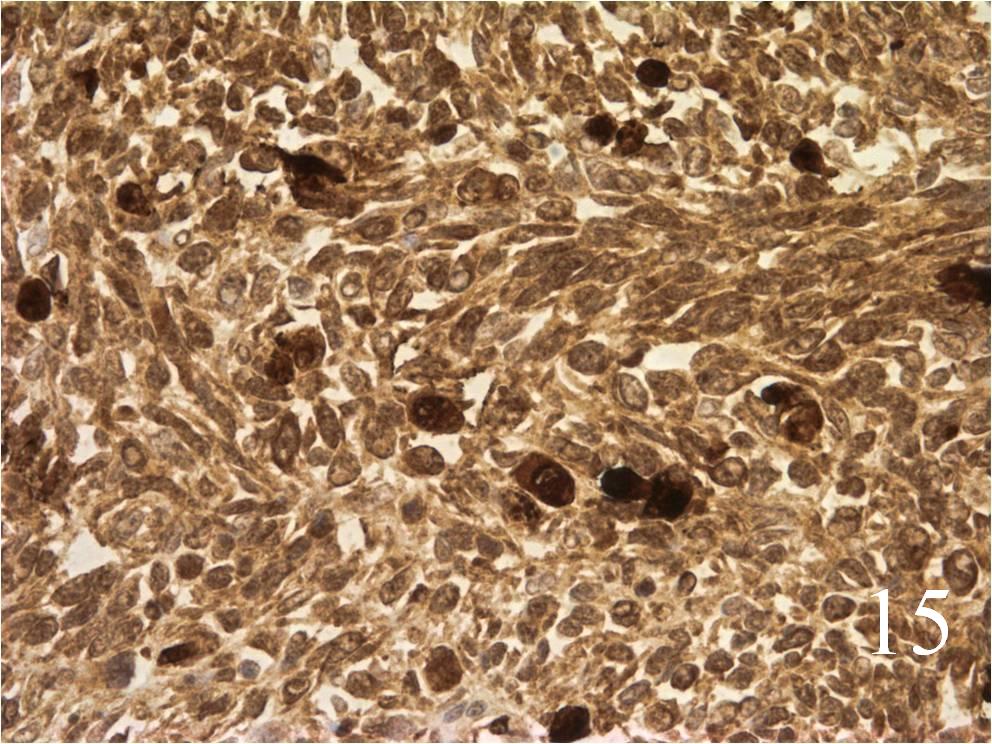

Microscopic

- Embryonal:

- Small round blue cells (Fig. 12-15)

- Round, oval, polygonal cells

- Fibrotic/myxoid stroma

- Rhabdomyoblast: well differentiated will have cross striations

- Alveolar:

- Tumor cells grow in nest or clusters

- Identify rhabdomyoblasts with cross striations

- Pleomorphic:

- Essentially identical to pleomorphic MFH

- Admixture of spindle-shaped, pleomorphic polygonal, round cells

- Arranged in fascicular, storiform, and patternless pattern

- Nuclei is large, oval-round, and multiple.

Immunohistochemistry

- Vimentin positive; Keratin negative

- Actin variable; perhaps minor scant staining

- S-100 negative